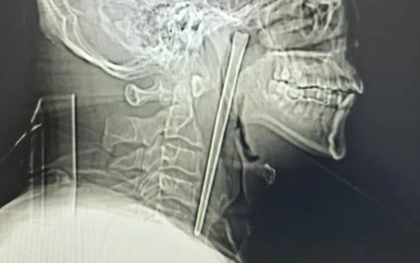

Người phụ nữ 55 tuổi xuất hiện cảm giác đau, vướng vùng cổ họng, khó chịu kéo dài nên được người nhà đưa đến viện. Bác sĩ gắp phát hiện "thủ phạm" bên trong.